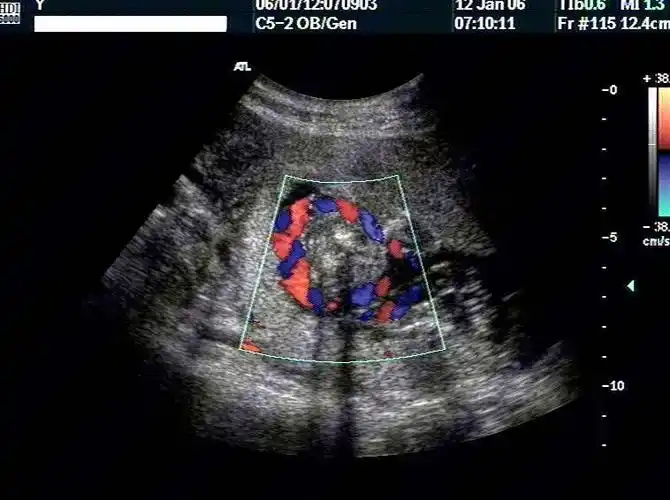

典型脐带绕颈(2周) - 超声医学讨论版 - 爱爱医医学论坛

脐带缠绕超声如图所示:脐带绕颈对胎儿的影响视其缠绕松紧程度而不同

52:48 胎儿纵切面见"u"形脐带压迹,横切可见脐带呈360度彩色血流环绕